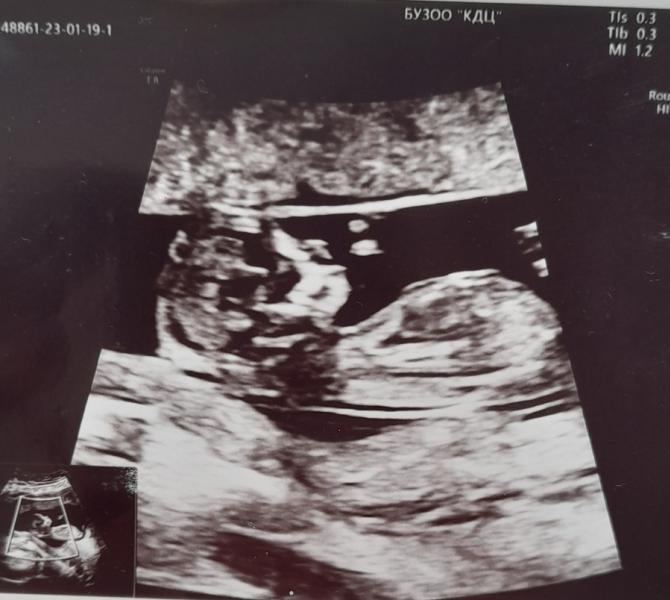

Была на первом скрининге... срок поставили на 4 дня больше.

Ииии у нас ЧЕТВЕРТАЯ ДОЧЬ!!!🥰😂😍правда ещё не 100%, но я думаю, что уже ничего не изменится, с третьей так же на этом сроке сказали!!!